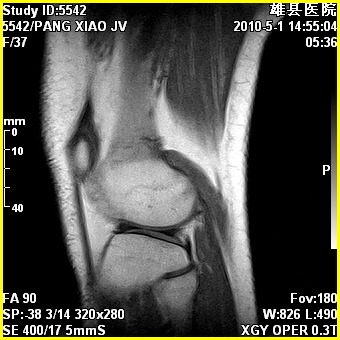

标题: MRI2894:患者右膝关节疼痛两月余,无明显外伤史 [打印本页]

标题: MRI2894:患者右膝关节疼痛两月余,无明显外伤史

右股骨下端前内侧类圆形异常信号,位于干骺端,呈长t1长t2改变,但信号不均,t1图上病灶中心见小片状稍高信号影,t2图上见散在稍低信号影,stir像呈高信号,因病灶较小,缺乏特征性改变,结合患者年龄及部位,考虑嗜酸性肉芽肿可能性大。胫骨关节面下的小囊状异常信号,如果一元论考虑则为嗜酸性肉芽肿,不过发生在这个部位的少见,二元论考虑为邻关节骨囊肿。半月板与前后交叉韧带均未见异常。

右股骨下端前内侧干骺端囊性良性病变,考虑 1内生软骨瘤 2骨囊肿 3肉芽肿。